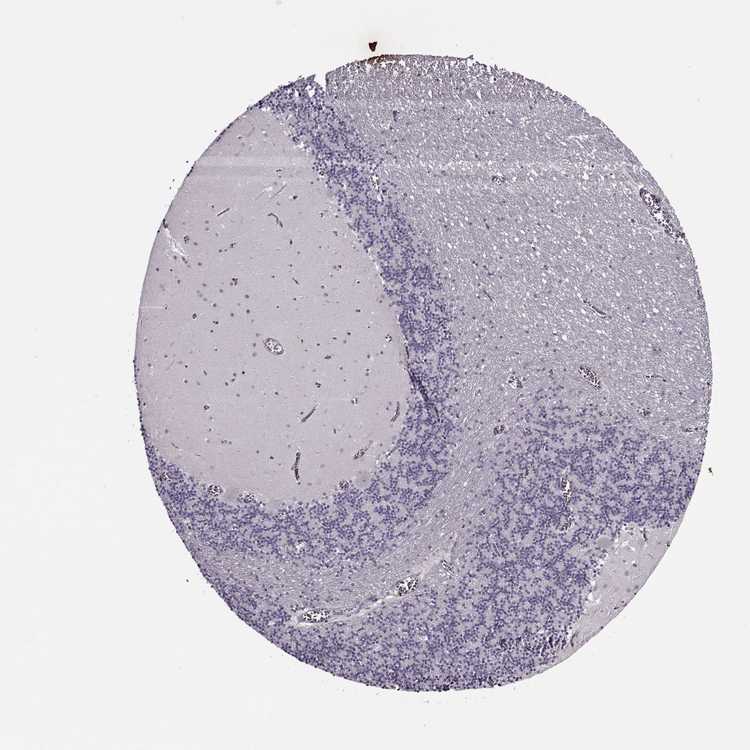

BRAIN CEREBELLUM Show tissue menu

CEREBELLUM - Expression summary

CEREBELLUM - Antibody stainingi

Antibody staining in the annotated cell types in the current human tissue is reported as not detected, low, medium, or high, based on conventional immunohistochemistry profiling in selected tissues. This score is based on the combination of the staining intensity and fraction of stained cells.

Each image is clickable and will lead to virtual microscopy that enables deeper exploration of all samples and also displays staining intensity scores, fraction scores and subcellular localization as well as patient and tissue information for each sample.

Antibody HPA007261Antibody CAB037322

Purkinje cells Not detectedNot detected

Cells in granular layer Not detectedNot detected

Cells in molecular layer Not detectedNot detected